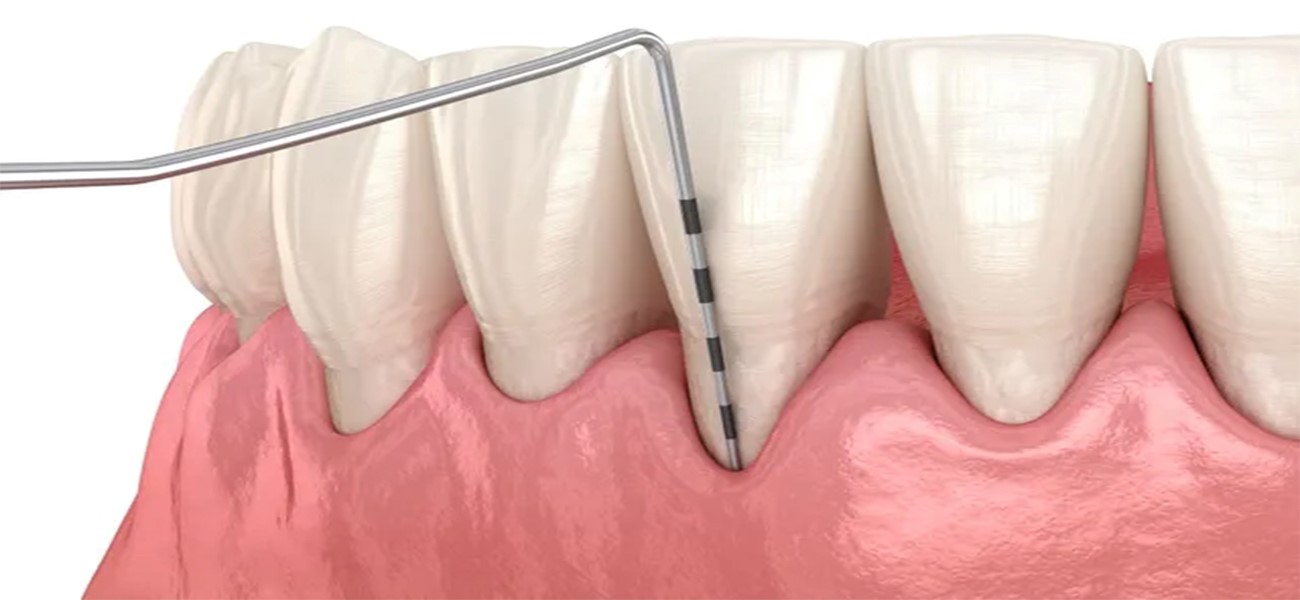

1. درمان بیماریهای لثه

یکی از اصلی ترین خدمات دکتر ندافپور، تشخیص و درمان بیماریهای لثه مانند التهاب لثه، پریودنتیت و دیگر مشکلات مربوط به بافتهای نرم دهان است. ایشان با استفاده از روشهای نوین و تجهیزات پیشرفته، قادر به ارائه درمانهای مؤثر و سریع هستند.